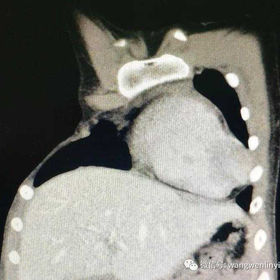

The chest wall exhibits asymmetry, with a concavity on the right side and an absence of the pectoralis major. Additionally, multiple costal cartilages are hypoplastic, leading to the formation of local defects. The patient was diagnosed with severe Poland syndrome.